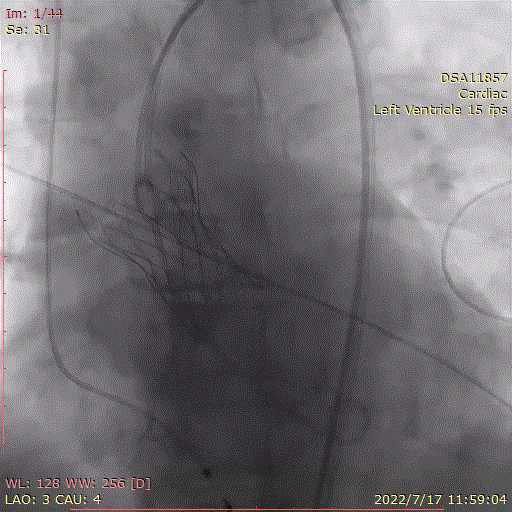

跨瓣角度为LAO 3° CAU 4°(右窦中心位),球囊预后扩角度为LAO 14° CRA 8°(左冠切线位);

术中首先行冠脉造影术,造影提示右冠近中段严重狭窄,于病变处植入支架一枚。植入后造影显示,无残余狭窄及夹层,前向血流TIMI3级。

冠脉造影,支架植入